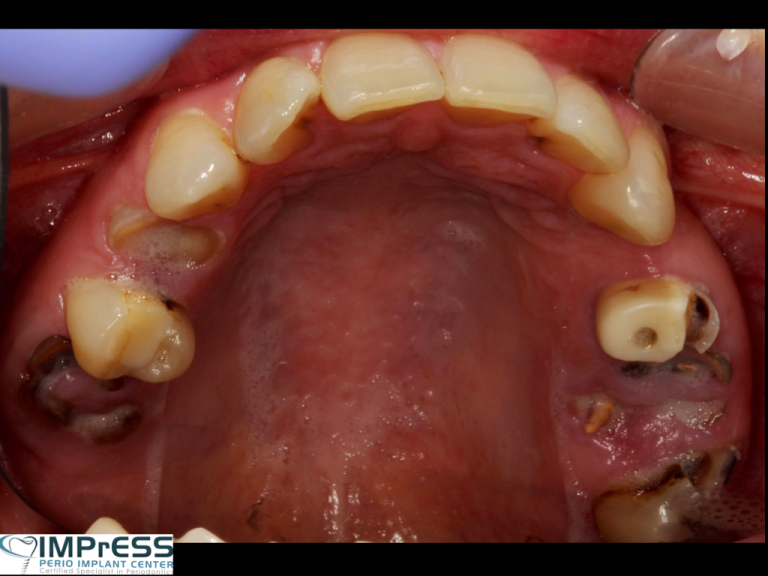

Full Mouth Reconstruction with Fixed Implant Bridge – All on X